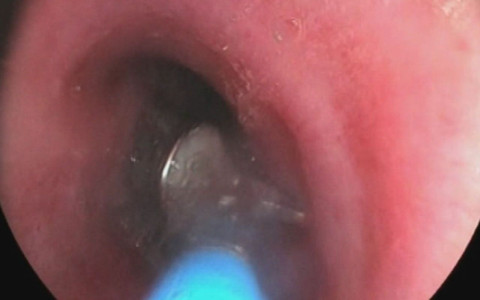

Galerinin tamamı için tıklayınızUruç, şöyle devam etti: Hasta ilk bize geldiğinde ciddi bir nefes darlığı olmadığı için parçanın yemek borusu veya midesine takılmış olabileceğini düşündük. Endeoskopide yemek borusunda herhangi bir problem yoktu. Tekrar filmleri değerlendirdiğimizde hastanın içerisindeki implantın tomografik yöntemle nerede olduğunu tespit ettik.